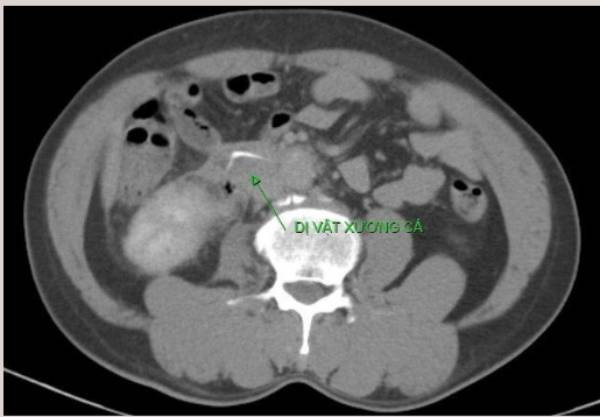

Tại Trung tâm Y tế Trường Sa, thông qua hội chẩn Telemedicine với các bác sĩ tại Bệnh viện Quân y 175 kết hợp siêu âm bụng, bệnh nhân được chẩn đoán có dị vật ở tá tràng, rất có thể là tăm tre hoặc vật thể có kích thước tương tự xuyên thành tá tràng gây đau bụng, có thể dẫn đến các biến chứng nguy hiểm, được chỉ định phải mổ để lấy dị vật.

Tại Bệnh viện Quân y 175, bệnh nhân được các y, bác sĩ nhanh tiến hành phẫu thuật nội soi gắp dị vật là xương cá ở D2 tá tràng.